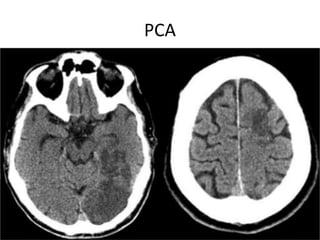

PCA